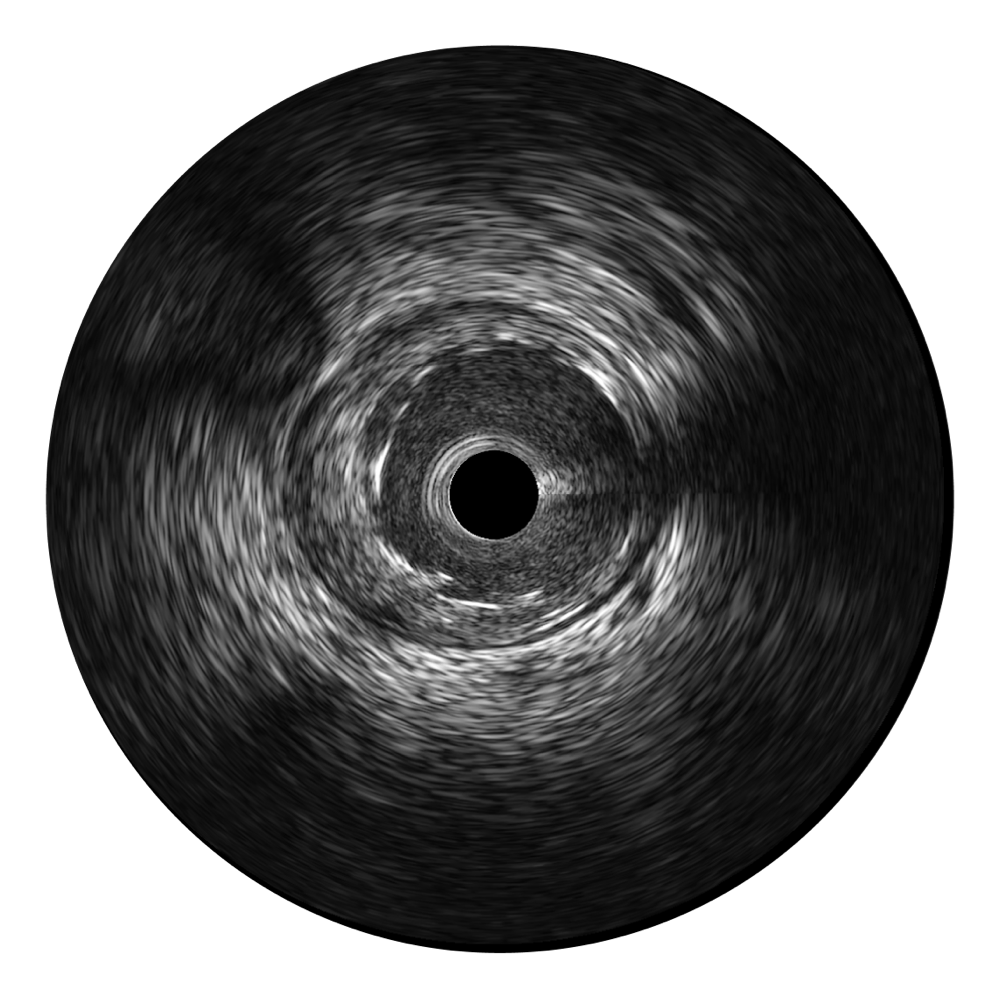

云顶集团官网宽频IVUS图像

传统IVUS图像

对比传统IVUS导管成像,云顶集团官网宽频IVUS图像的近场支架梁显影更细腻,远场中膜外血管仍清晰可辨,兼顾远中近,兼顾分辨力与穿透深度